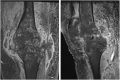

We present a case series comprising three patients with concomitant septic arthritis of the knee and osteomyelitis of the femur. Early advanced imaging rendered the accurate diagnosis of the condition and the appropriate surgical approach and technique used to treat the infection. Repeated extensive surgical debridement, irrigation and insertion of antibiotic-impregnated cement rod into the femur were required, in addition to long term antibiotics. The infection in all three cases was eradicated successfully. Following a period of physical rehabilitation, they had fairly preserved independent ambulatory function. We advocate a high index of suspicion of this condition with subsequent early advanced imaging for a timely diagnosis. In addition, we described our challenges in the fabrication process of the antibiotic-impregnated cement rod.